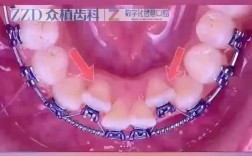

活动牙齿矫正器是一种可由患者自行摘戴的口腔正畸装置,主要通过施加温和、持续的力来引导牙齿移动,改善排列不齐、咬合异常等问题,相较于固定矫正器,其优势在于佩戴灵活、便于清洁,尤其适用于儿童早期干预、青少年简单错颌及成人轻度矫正需求,本文将从活...